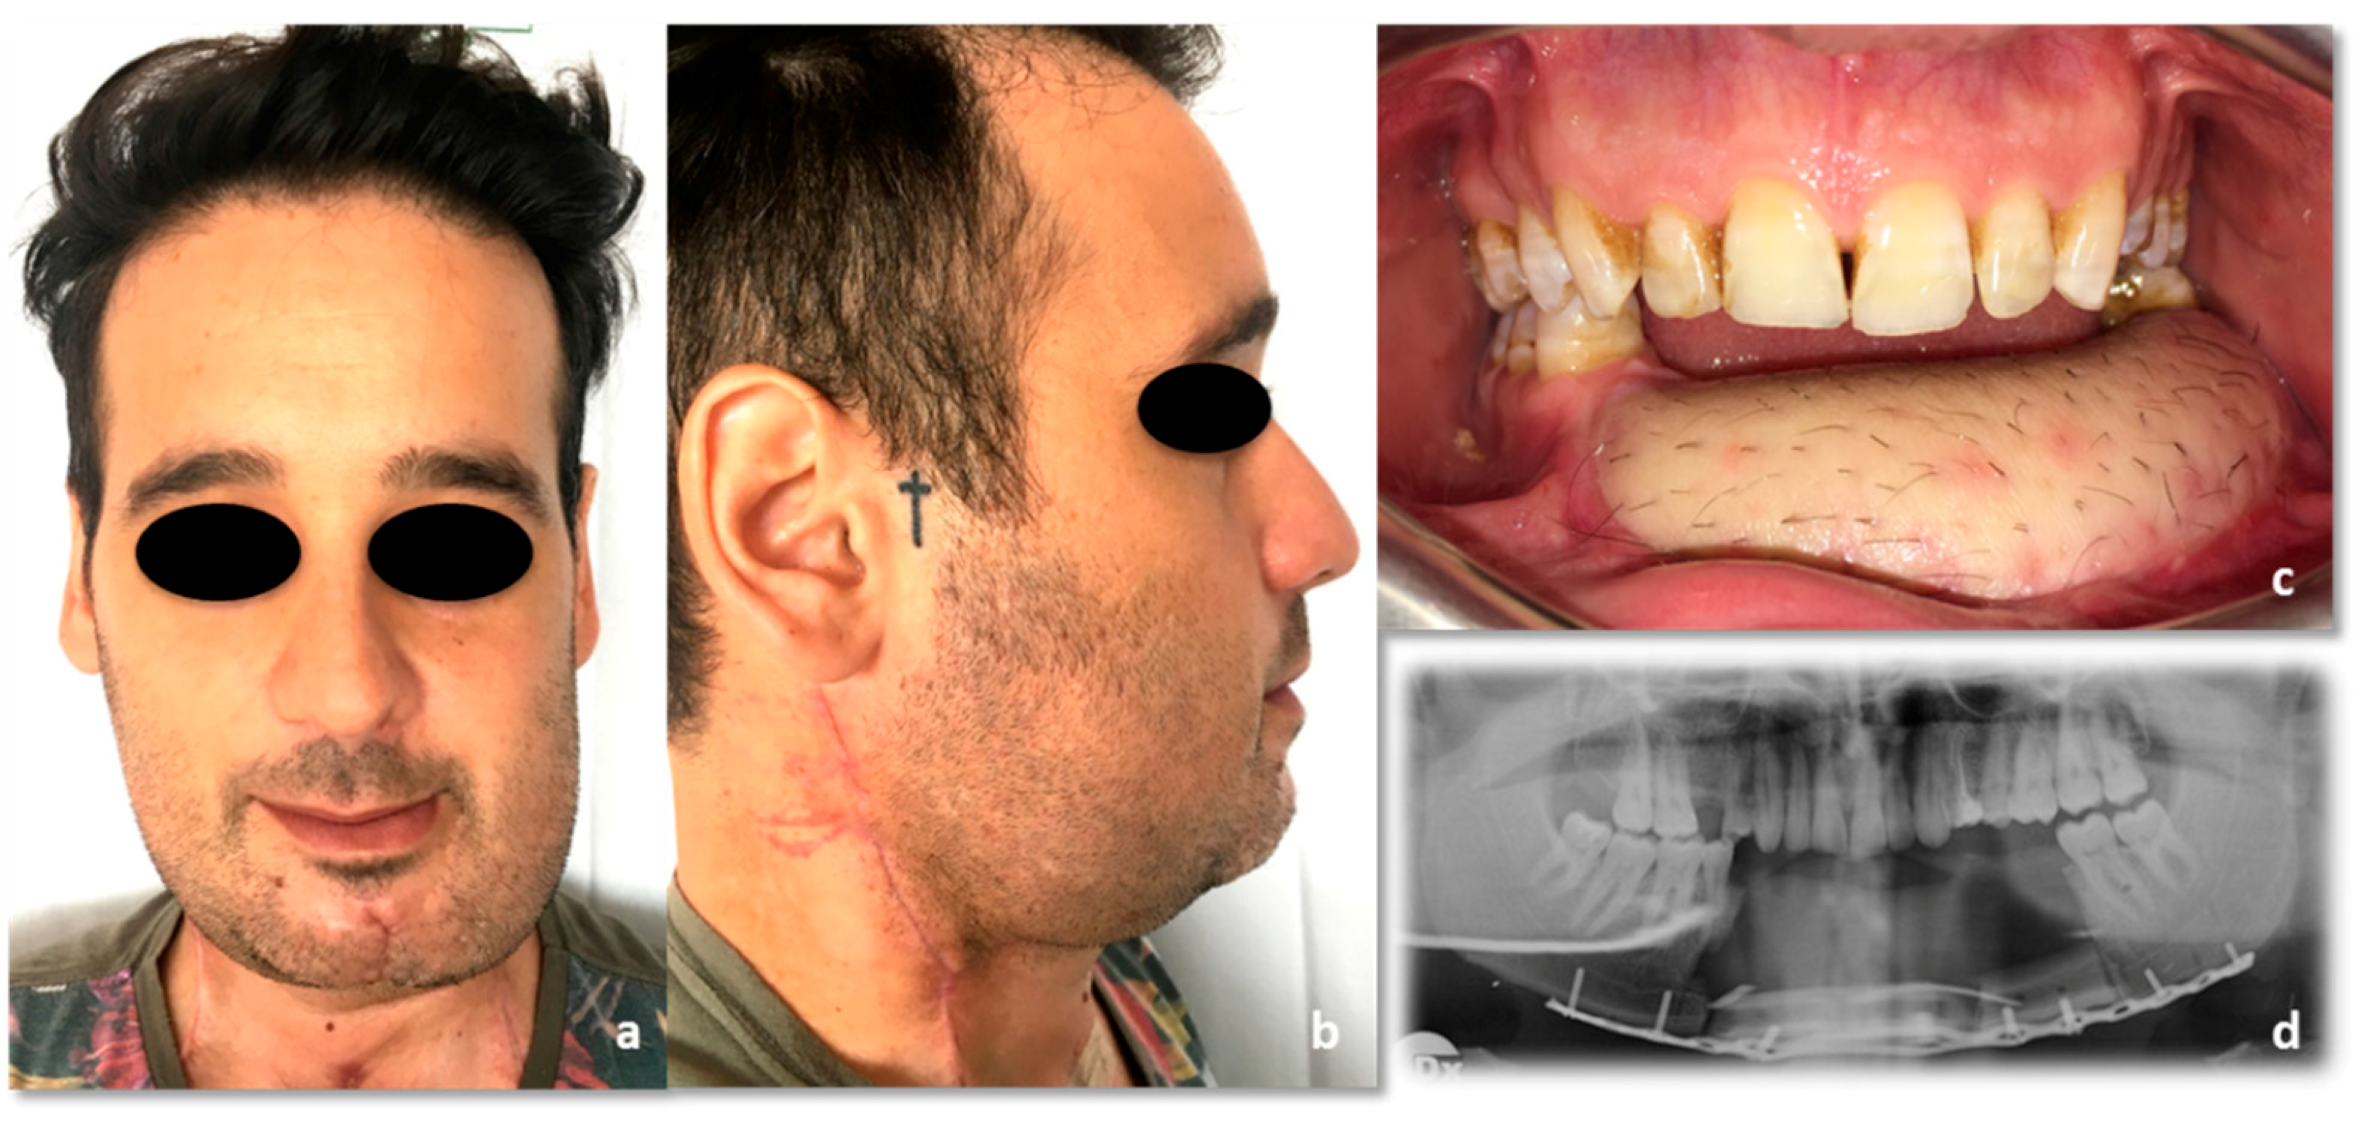

The patient’s case was debated at our local head and neck cancer multidisciplinary team meeting to plan adjuvant radiotherapy. After the third RT cycle (two months after the surgery), the patient developed an aching swelling in the left cheek, even though he had already started the treatment. Given the worsening of the symptoms following the antibiotic therapy, an ultrasound examination was performed, demonstrating a 3 cm diameter hypo-anechoic avascular lesion anteriorly to the left masseter muscle. An echo-guided biopsy was performed, and the histological exam showed the presence of G3 squamous cell carcinoma fragments. A salvage surgical excision was performed, completely removing the lymph node with clear margins, although extracapsular spread was documented in the final report. Given this new finding, a further head and neck cancer multidisciplinary team meeting made an indication for radiotherapy restart together with cisplatin-based chemotherapy at a dose of 40 mg/m2/day per cycle, which were successfully completed (Figure 12). The patient ended its surgical and radiochemotherapy oncological treatment within 6 months from the initial diagnosis (Table 2).

Figure 12.

Post-radiochemoterapy follow-up. (a) Frontal view; (b) side view; (c) intraoral picture; (d) CT, coronal view.

The patient has had a follow-up every 3 months ever since. No tumor recurrence was detected at the 31-month follow-up. His actual quality of life is good, and the patient is pretty satisfied with the aesthetic and functional outcomes, including facial nerve function that has remained entirely normal (Figure 13) (Video 2 in supplementary file). He only referred a minimal temporo-mandibular joint discomfort two-years after treatment, treated successfully with a functional approach. The next therapeutic step should be the infiltration of the radio-treated tissues with autologous fat, in order to improve the lower face contour and the skin texture.

Figure 13.

Thirty-one-months follow-up. (a) Frontal view. (b) side view. (c) intraoral picture. (d) 3D CT reconstruction.